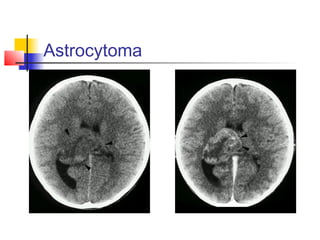

1. ASTROCYTOMAS

 Arise around the ventricles and invading

into them.

 The commonest site is the thalamus.

 The clinical features are according to the

location, size, and infiltration.

 CT and MRI: like astrocytomas elsewhere.

 Tissue diagnosis is essential (stereotactic

biopsy). Debulking is considered. Radiation

and chemotherapy may be beneficial.

Astrocytoma